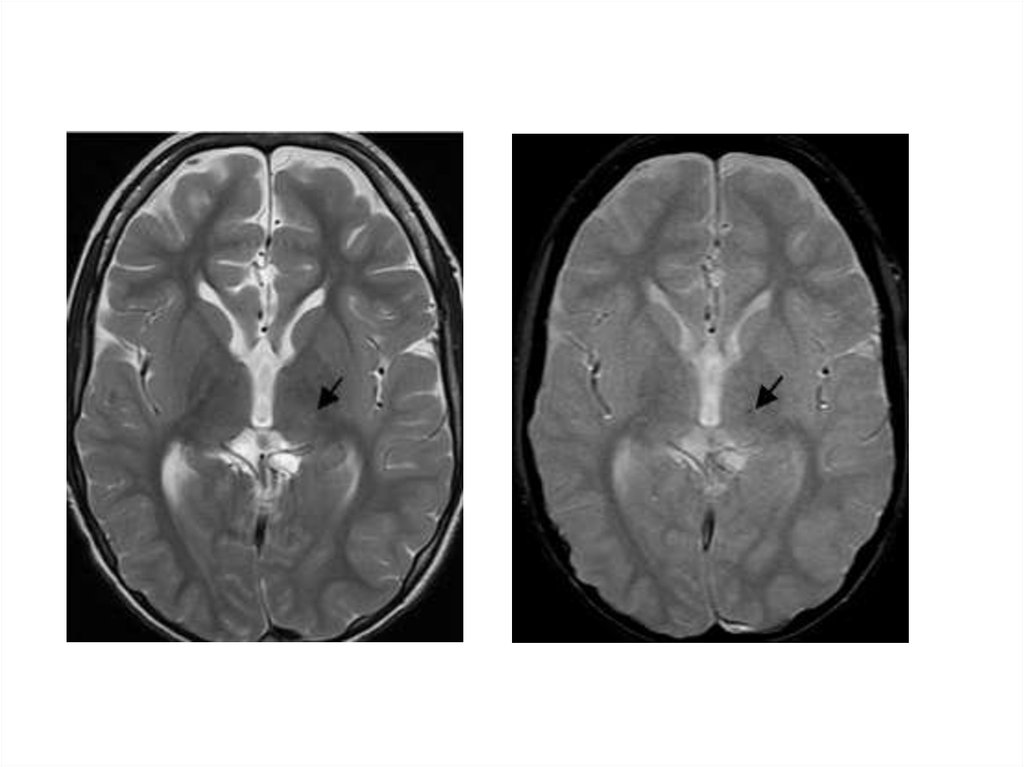

46. Церебральная кавернозная венозная мальформация (кавернозная гемангиома)

48 – 86% - в полушариях

5 – 13% сосудистых мальформаций ЦНС

Манифестирует в 40-60 лет

Клиническая картина: обмороки (60%),

неврологический дефицит (50%),

кровоизлияния (20%), гидроцефалия

(50%)

47.

48.

49.